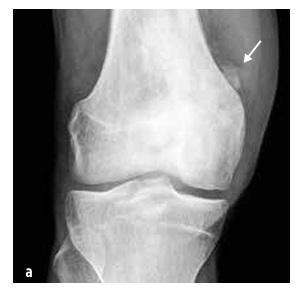

Obrázok 2

Porovnanie distribúcie kostných lézií na MRI u detí s CRMO a septickou osteomyelitídou (podľa Schnabel et al., 2016)

Najčastejšie postihnutými kosťami sú metafýzy dlhých kostí, kľúčna kosť, telá stavcov a panva (pozri obrázok 2). Počet kostných lézií sa líši (niekedy ide len o jednu léziu, častejšie o viacero lézií). Niekedy sa aj asymptomatické lézie odhalia pomocou kostnej scintigrafie alebo magnetickej rezonancie celého tela (WB MRI).